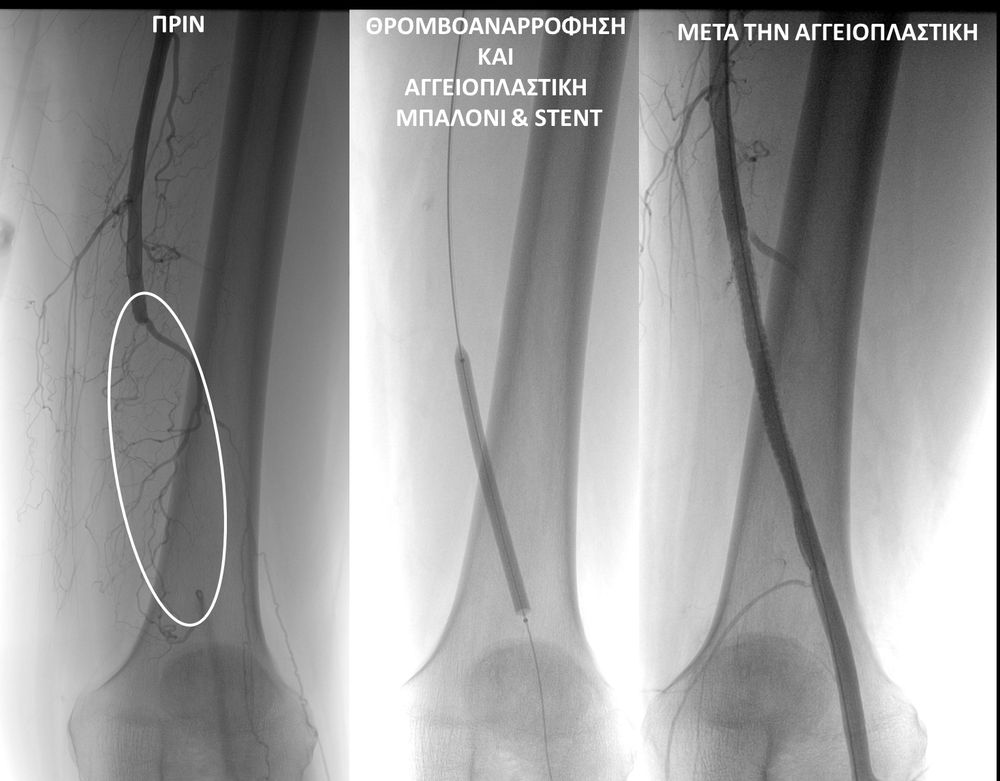

• Η αγγειοπλαστική των αρτηριών είναι μία μη χειρουργική επέμβαση που αποσκοπεί στη διάνοιξη των στενωμένων ή αποφραγμένων αρτηριών. Γίνεται με την ίδια τεχνική όπως και αγγειογραφία. Η αγγειοπλαστική των αρτηριών μπορεί να γίνει είτε με απλή διάνοιξη της αρτηρίας που εμφανίζει στένωση με μπαλόνι ή και να συνοδευθεί από τοποθέτηση ενδαγγειακής πρόθεσης (stent).